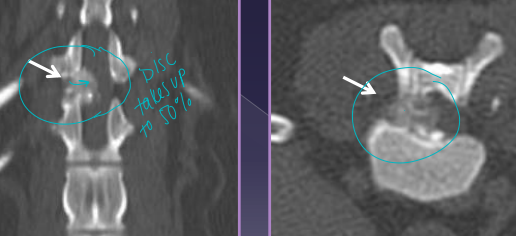

Herniation (Hansen Type I) Acute → fast progressive

Sig: chondrodystrophics, 3-5y (TL) T10/11-L6/7 ¾ dogs

Cs: Compressive myelopathy, Contusion injury

Dt: CT/MRI (#1), Rads(r/o) (narrowing, wedging, mineralized disc in SITU)

Tx: percutaneous laser disc ablation(prevent T10/11-L5/6), >4w rest, NSAID, gabapentin, amantadine, ventral slot Sx (C), Hemilaminectomy (TL)